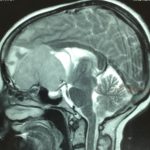

Cette masse peut entrainer notamment :

- Une irritation du cerveau qui se manifeste par une épilepsie

- Une compression voire destruction d’une partie du cerveau causant un affaiblissement ou une perte d’une fonction du cerveau

- Une augmentation de la pression à l’intérieur du crâne (espace inextensible à l’intérieur duquel vient s’ajouter le volume de la tumeur), ce qui va se manifester initialement par des maux de tête d’aggravation progressive qui vont s’associer à des nausées, des vomissements, des troubles visuels… Cet état peut aboutir à la perte de la vue dans les formes d’évolution lente et au décès dans les formes d’évolution rapide.